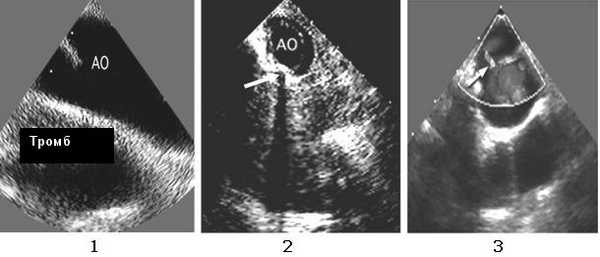

Транспищеводная ЭхоКГ обладает 93% чувствительностью, 100% специфичностью и прогностической ценностью. Главное преимущество этого исследования - его мобильность: гемодинамически нестабильный пациент может подвергнуться диагностической лапаротомии или другим процедурам, одновременно с транспищеводным ЭхоКГ исследованием. Риск его низок, поэтому противопоказанием является только травма шейного отдела позвоночника или пищевода. Doppler эхокардиография используется для оценки изменения кровотока, связанных с формированием клапана интимы.

Транспищеводная ЭхоКГ: парааортальный тромб (1); расслоение аорты в области перешейка (2); допплерография - турбулентный поток в области перешейка вследствие образования клапана интимы (3).